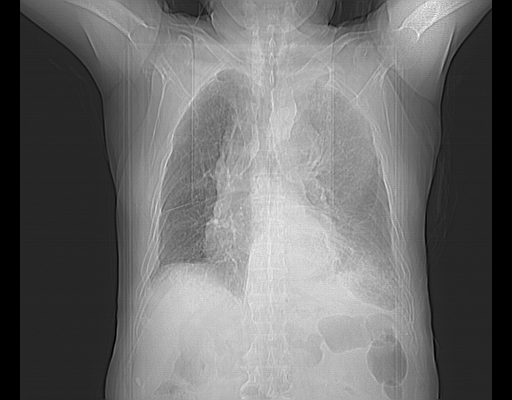

CT50521:男,88岁,反复咳喘10余年:

男,88岁,反复咳喘10余年,再发加重伴咯血10天。

考虑左下肺周围型肺癌并阻塞性肺炎,纵隔淋巴结转移,左侧胸膜转移

。2)慢性支气管炎并肺部感染,肺气肿。3)双侧胸腔积液,以左侧为甚。4)升主动脉及主动脉弓钙化。

考虑左肺纵膈性肺癌并纵膈、心包周围淋巴结转移,胸膜转移,建议胸水化验

考虑左侧占位,胸腔积液。

左下肺阻塞性病变并左侧胸腔积液。